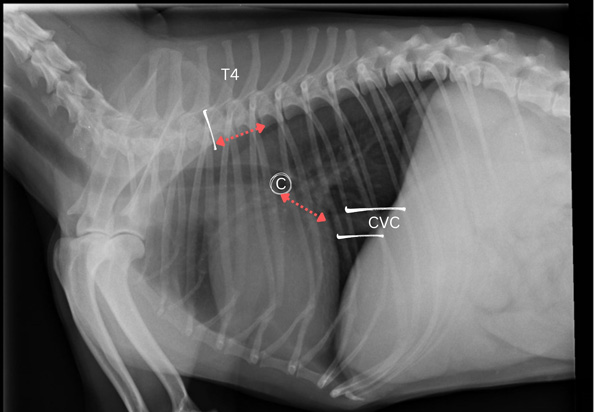

Figure 3: VLAS. Lateral thoracic radiograph with carina (c), caudal vena cava (CVC), and spinous process of the fourth thoracic vertebra (T4) identified. Distance is measured from the carina to the dorsal border of the caudal vena cava at the site where it intersects the caudal aspect of the cardiac silhouette (red line). This measurement is expressed in terms of vertebral body units using the cranial border of the fourth thoracic vertebra as the starting point.

To measure VLAS:

- Use the same good quality lateral thoracic radiograph centred over the heart.

- Identify the caudal vena cava – a thick, soft-tissue opacity vessel running through the caudal thoracic cavity.

- Measure from the ventral aspect of the carina to the dorsal border of the caudal vena cava at the site where it intersects the caudal aspect of the cardiac silhouette.

- Express this distance in terms of VBUs, again using the cranial border of the fourth thoracic vertebra as the starting point11.